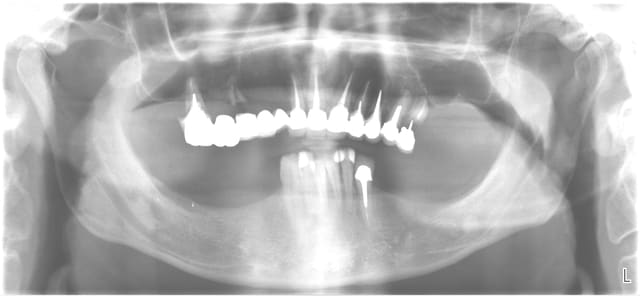

Cas clinique à venir, extraction et mise en charge immédiate du maxillaire supérieur.

Mci qoq4vl - Eugenol

MCIPE au maxillaire supérieur

cas Pluton 01

cas Pluton 02